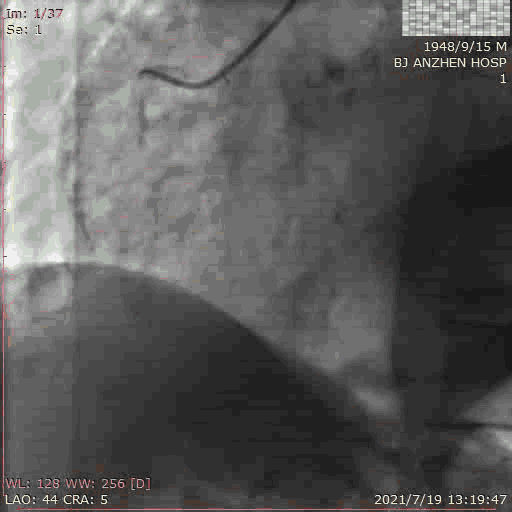

TAVR过程:患者局麻后,植入临时起搏器,穿右股动脉送入23mm球囊预扩张病变,左、右冠状动脉未受明显影响,决定直接植入爱德华SAPIEN 3 26mm 球扩式瓣膜,选择标准位进行释放。

释放后主动脉窦造影提示瓣膜膨胀良好,主动脉瓣周少量反流。术后即刻TTE提示跨瓣最高流速109cm/s,平均跨瓣压差3mmHg。主动脉瓣瓣口面积2.72cm²。